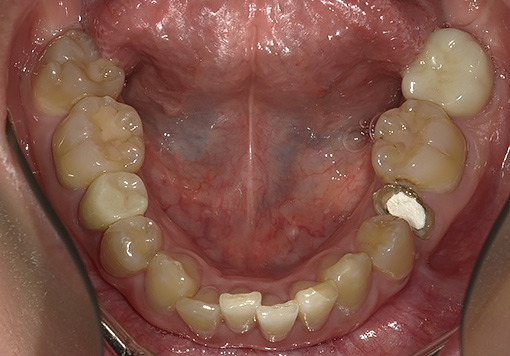

Case 01

before

after

- 主訴:歯並びが気になる

- 治療内容:下顎のみマウスピース矯正

- 治療期間:1年間6ヶ月

- 診断結果:歯列不正

- 治療後経過:経過良好

- 治療費用:40万円

リスク・副作用:歯肉退縮、歯の動揺、歯根吸収